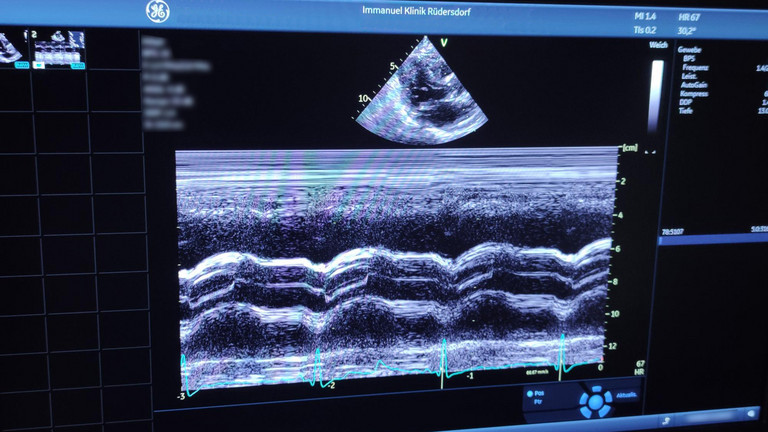

- Ultraschalluntersuchung des Herzens (Echokardiographie) und der Gefäße

- Ultraschalluntersuchung des Herzens von der Speiseröhre aus (Transösophageale Echokardiographie - TEE)